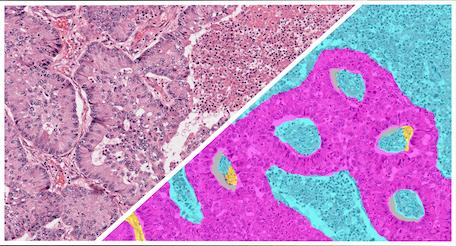

The Gastric H&E Tumor Tissue Detection App is a pre-trained HALO AI masking classifier designed to segment tumor, stroma, necrosis/other, and glass areas across H&E-stained whole slide images of gastric cancer.

The Head & Neck Squamous Cell Carcinoma (HNSCC) H&E Tumor Tissue Detection App is a pre-trained HALO AI masking classifier designed to segment tumor, stroma, necrosis/other, and glass area across H&E-stained whole slide HNSCC images.

The Non-Small Cell Lung Cancer (NSCLC) H&E Tumor Tissue Detection App is a pre-trained HALO AI masking classifier designed to segment tumor, stroma, necrosis/other, and glass area across H&E-stained whole slide images of NSCLC.

The Ovarian H&E Tumor Tissue Detection App is a pre-trained HALO AI masking classifier designed to segment tumor, stroma, necrosis/other, and glass area across H&E-stained whole slide images of ovarian cancer.